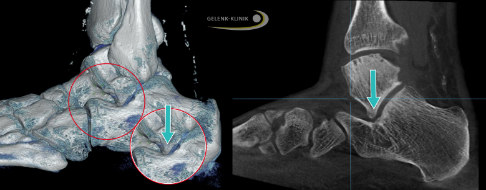

Dieses Bild zeigt eine komplexe Knick-Senkfuß-Deformität aus zwei Perspektiven. Von hinten (links) erkennt man eine Lücke zwischen Sprungbein und Fersenbein (Aufklappung), wobei das Fersenbein nach außen abweicht. Die Achse zeigt die vorhandene Deformierung. Rechts blickt man von vorne schräg oben auf den Fuß. Hier sieht man die deutliche Drehung des Sprungbeins nach innen. Der Sprungbeinkopf rutscht als Folge der Instabilität am Fersenbein vorbei. © Gelenk-Klinik

Knick-Senkfuß von außen (links 3-D, rechts CT). Das Sprungbein (Talus) ist so abgesenkt und rotiert, dass es zu einem Anschlagen an das Fersenbein (Calcaneus) kommt (talocalcaneares Impingement). Der Pfeil zeigt auf die Kontaktzone. © Gelenk-Klinik

Knick-Senkfuß von innen (links 3-D, rechts CT). Durch Verschiebung des Rückfußes hat sich das Sprungbein abgesenkt. Als Überlastungsreaktion zeigt sich ein Einknicken im Tarsus zwischen Kahnbein und Keilbein. Der linke Pfeil zeigt die Instabilität zwischen Sprungbein und Fersenbein, der Pfeil von oben den Kollaps im Fußwurzelbereich. © Gelenk-Klinik